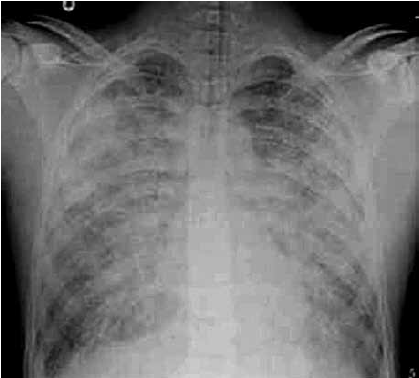

Exame de imagem:

(Disponível em: https://resources.wfsahq.org/ atotw/sindrome-do-desconforto-respiratorio-agudo/)